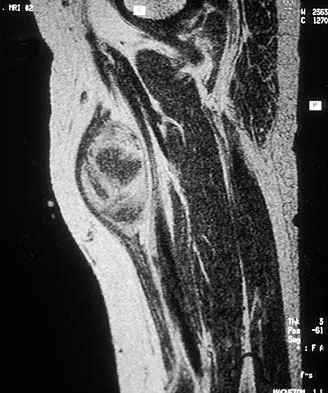

A 40-year-old man has a palpable mass over the dorsum of the ankle. He reports no history of direct trauma but notes that he sustained a laceration to the middle of his leg 6 weeks ago. Examination reveals a 4-cm x 1-cm mass. T1- and T2-weighted MRI scans are shown in Figures 12a and 12b. An intraoperative photograph and biopsy specimen are shown in Figures 12c and 12d. What is the most likely diagnosis?